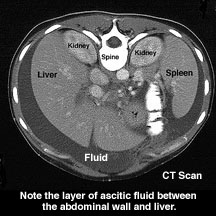

ascites

An abnormal accumulation of serous, peritoneal fluid in the abdominal cavity, usually caused by liver disease (~80% of cases) and exhibiting reduced synthesis of albumin and other oncotic plasma proteins (proteins which contribute to the osmotic = oncotic pressure of the blood), and less often caused by heart or kidney diseases or pancreatitis.

Image: ascites

Cirrhosis of the liver

is a common cause of

ascites in liver disease

patients, often suffering

from chronic alcoholism.